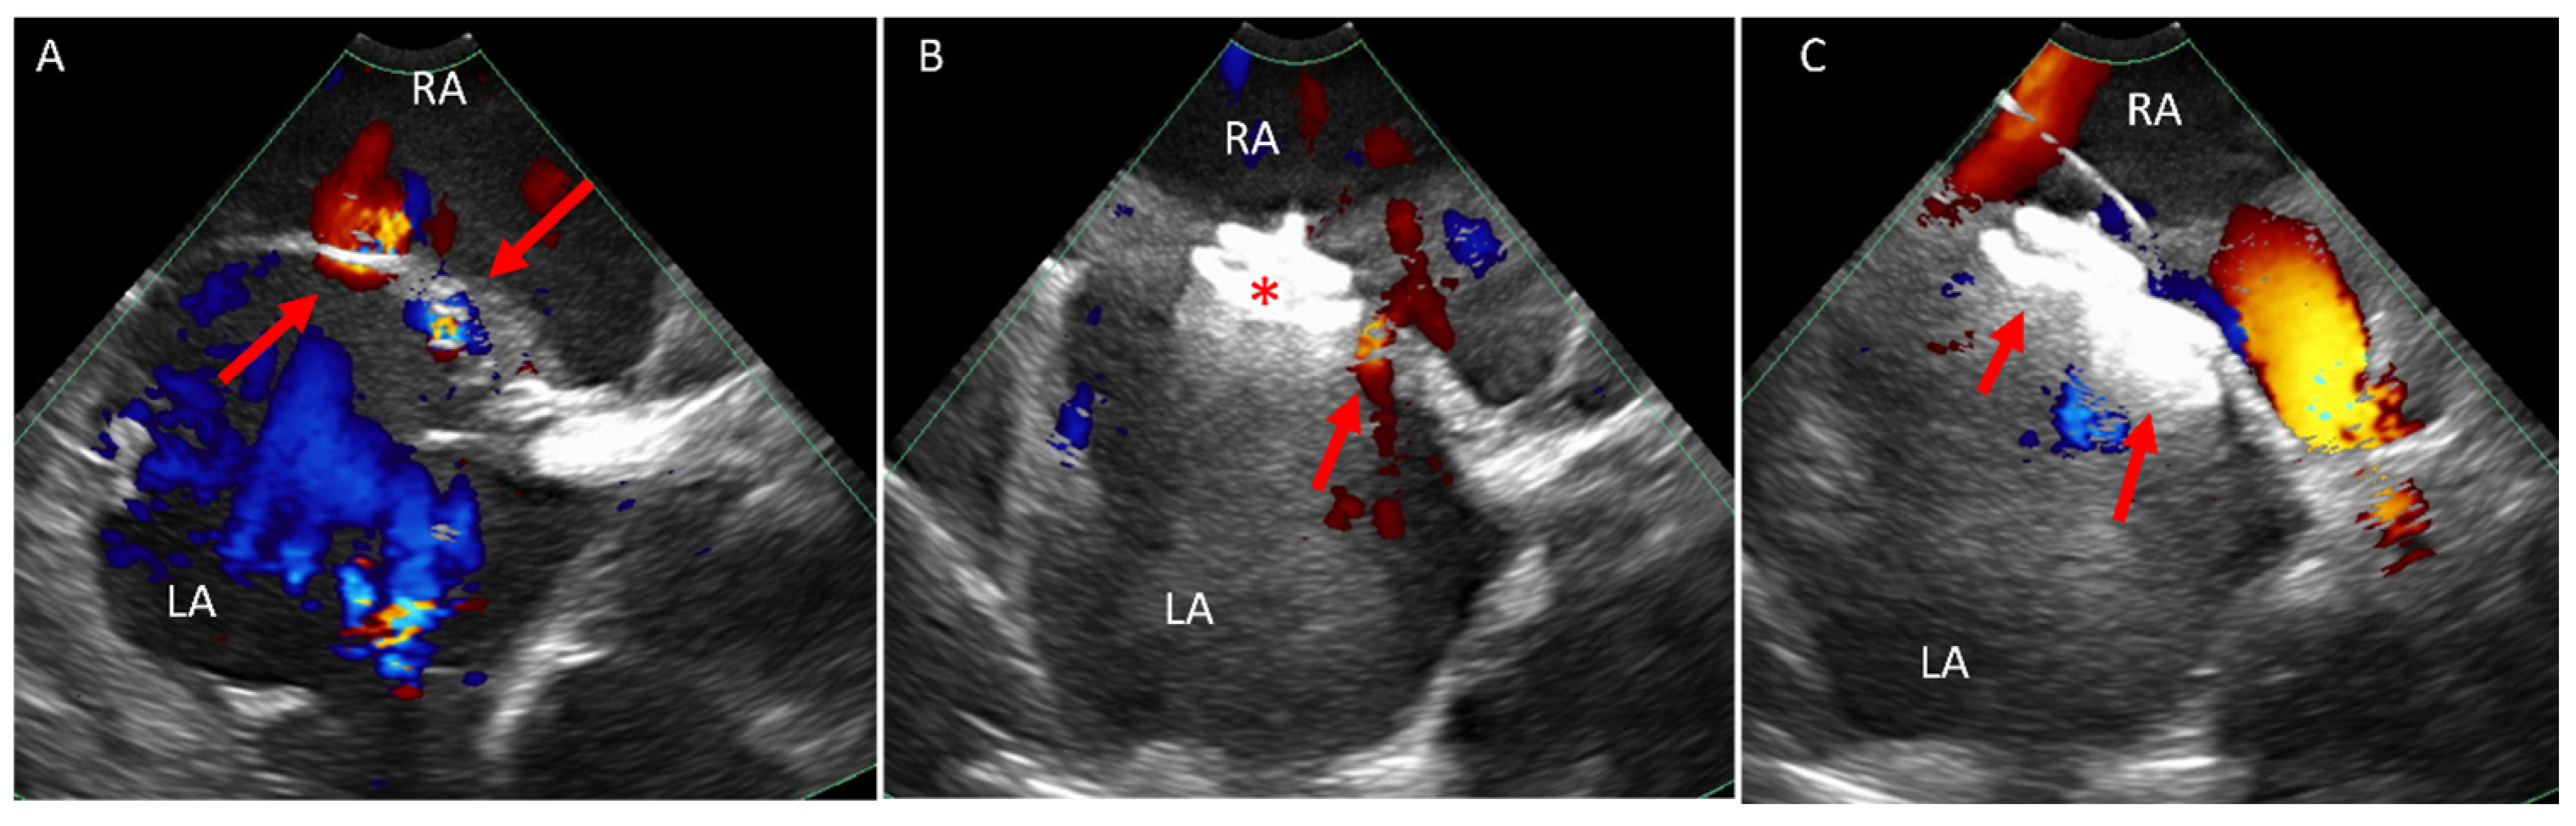

5.1. Paravalve Leak (PVL) Occlusion